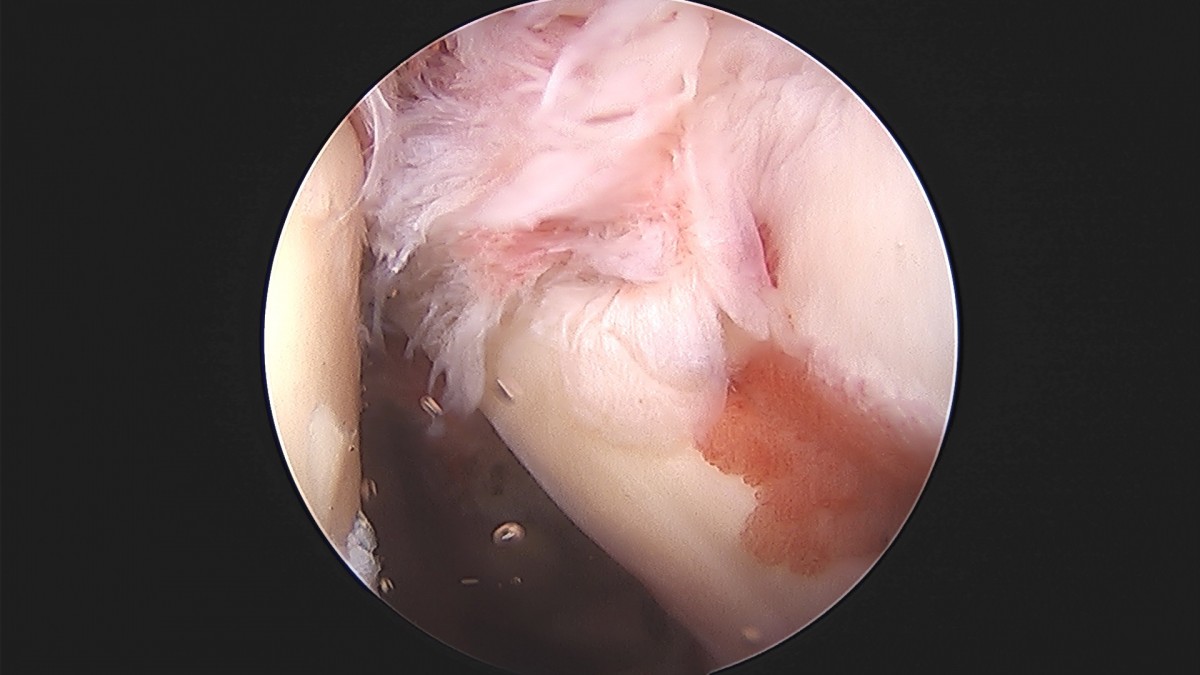

이재상원장님 어깨 견봉하 감압술 및 관절낭 이완술 박창O 환자

dae765e4d9ac96aee867c9d6292d8784_1758004611_6449.jpg